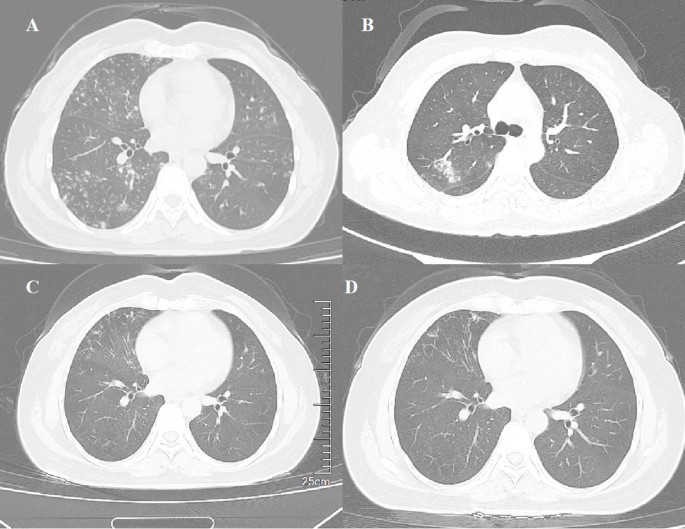

Views of computed tomographic scan of the chest at different stages of disease. Chest computed tomography (CT) scans show multiple centrilobular nodules in both lungs, with some presenting a tree-in-bud appearance and some presenting as patchy ground-glass opacities, and traction bronchiectasis in the middle lobe of the right lung on July 26, 2021 (A); new patchy ground-glass opacity in the upper lobe of the right lung on April 3, 2023 (B); multiple centrilobular nodules in both lower lungs on July 28, 2023, with significant reduction compared to previous images (C); multiple centrilobular nodules in both lower lungs further reduced and absorbed, along with a decrease in traction bronchiectasis in the right middle lobe on June 18, 2024 (D).

On physical examination, bilateral coarse breath sounds were noted, with a few moist rales in the lower lung fields. Laboratory investigations revealed no significant abnormalities in routine blood tests, C-reactive protein (CRP) and procalcitonin. Initial bacterial smears showed Gram-positive cocci and Gram-negative bacilli, but no acid-fast bacilli were detected. The tuberculosis γ-interferon test was negative. Thyroid function tests revealed elevated thyroid peroxidase antibodies (398.1 U/mL), an erythrocyte sedimentation rate (ESR) of 22 mm/h, and a positive purified protein derivative (PPD) test with a 10 mm induration. Thyroid ultrasound indicated diffuse thyroid disease suggestive of Hashimoto’s thyroiditis. Chest CT demonstrated scattered nodules and high-density spots in both lungs, along with traction bronchiectasis in the right middle lobe (Fig. 1A).

The patient was treated with clarithromycin (1,000 mg every other day), rifampin (600 mg every other day), and ethambutol (750 mg every other day), as the mNGS on August 6, 2021 (refer to the mNGS analysis section) indicated the presence of NTM. The treatment continued for 17 months. In April 2023, chest CT revealed new patchy ground-glass opacities in the right upper lobe and increased bilateral lung inflammation (Fig. 1B). T cell subsets in the blood showed increased helper T lymphocytes (45.14%) and decreased cytotoxic T lymphocytes (12.93%), with the absolute count of cytotoxic T lymphocytes being 258.69 cells/µL. CD3 + CD4+/CD3 + CD8 + ratio was 3.49 (normal 0.7–2.8). Considering the absence of significant clinical improvement after a 17-month antibiotic regimen, and in light of recommendations from clinical practice guidelines of leading international respiratory medicine and infectious diseases societies39 as well as empirical regimens for Mycobacterium paraffinicum40the treatment was subsequently was adjusted to include amikacin (0.4 g daily, IV), azithromycin (0.5 g daily), ciprofloxacin (1,000 mg daily), and linezolid (600 mg twice daily). By July 28, 2023, the patient’s symptoms had improved, with significant absorption of lung lesions on chest CT, though right middle lobe bronchiectasis persisted (Fig. 1C). The treatment regimen was continued with azithromycin (0.5 g daily), ciprofloxacin (1,000 mg daily), and linezolid (300 mg twice daily), which has been ongoing for a year. The most recent CT scan on June 18, 2024, showed further reduction and absorption of multiple centrilobular nodules in both lower lungs, along with a reduction in traction bronchiectasis in the right middle lobe (Fig. 1D).